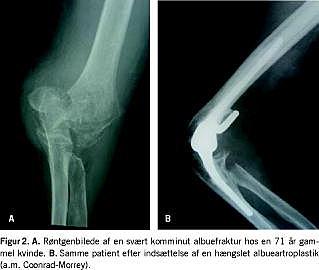

Langt den hyppigste indikation for indsættelse af albueartroplastik er destruktion af leddet pga. reumatoid artritis, idet en betydelig del af patienterne med reumatoid artritis kan forventes at få invaliderende smerter i albuen [5]. Traditionelt har man foretaget interpositionsartroplastik eller synovektomi og resektion af caput radii hos disse patienter, men total albueartroplastik har nu i vid udstrækning erstattet dette indgreb (Figur 1 ) [6]. Også hos yngre patienter med juvenil reumatoid artritis kan der i visse tilfælde være indikation for indsættelse af en total albueartroplastik [8].